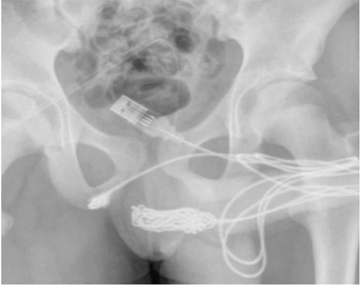

After an X-ray revealed the exact size and positions of the knot, the teen was sent to surgery.

Surgeons cut through the muscles surrounding the pen*s and scrotum and then severed and removed the knot.

Medics managed to extract the knot through the incision and then cut it free from the rest of the cable. The remaining two pieces of the cable were pulled out the opening of his pen*s once the knot was removed.